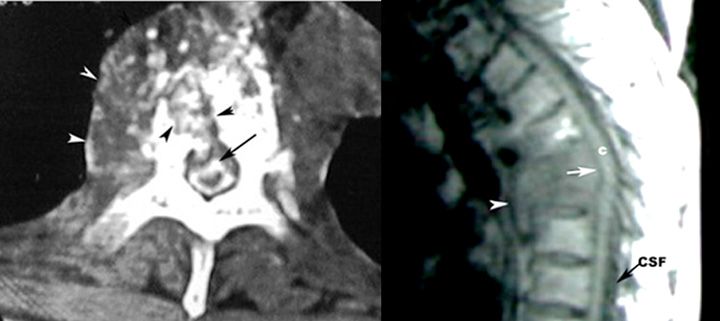

Tuberculosis Thoracic Spine With Paravertebral Abscess

CT

• White arrowheads point to paravertebral abscess.

• Black arrowheads point to destroyed vertebra.

• Black arrow points to contrast filled thecal sac, compressed by bony fragment.

• MR

• White arrowhead points to paravertebral abscess.

• White arrow points to compression of the cal sac by the destroyed vertebra.

• C: Cord

• CSF: cerebrospinal fluid